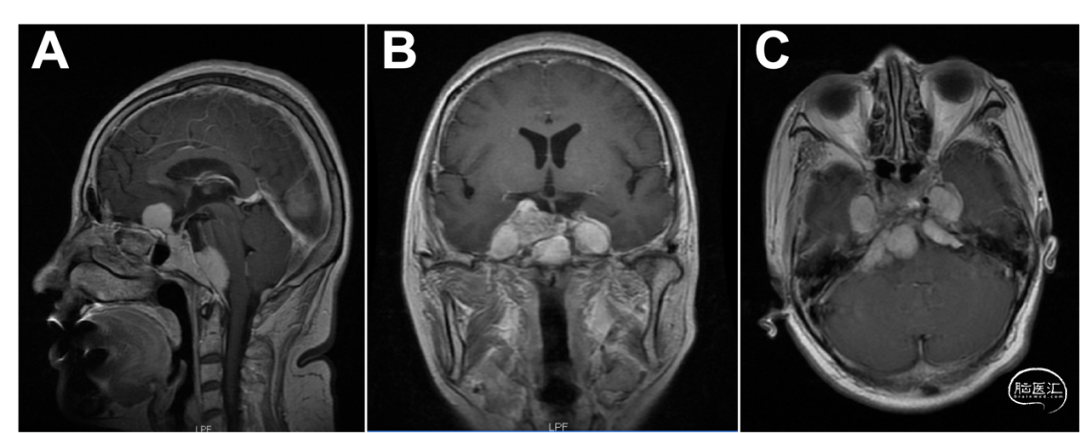

我院头颅MRI增强扫描:前中后颅窝多发占位,脑膜瘤考虑(图1)。

图1. 术前头颅MRI。 前中后颅窝可见多发大小不等异常信号结节,匍匐生长于颅底,于T1WI上为稍低等混杂,广基与颅骨内板相连,肿块突向脑实质一侧,其边缘可见低信号线状影与脑实质相隔,于T2WI上为低等混杂信号,增强扫描,肿块呈均匀明显强化,与颅骨接触处可见硬膜尾征,肿块周围水肿未见,具有占位效应,脑白质受压变形,皮层灰质向内移,邻近脑室变形移位,中线结构轻度右侧移位。颅脑其他部位无殊。